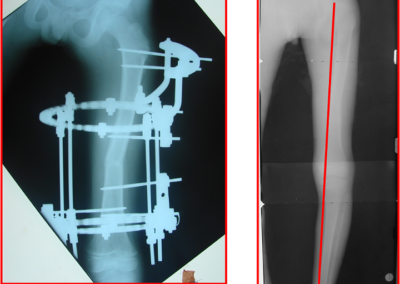

arthritis deformity surgery endoprosthesis hip prosthesis ilizarov ilizarov surgery infected nonunion knee prosthesis lengthening surgery limb lengthening surgery nonunion periprosthetic infection psodoartroz revision surgery total hip prosthesis total knee prosthesis